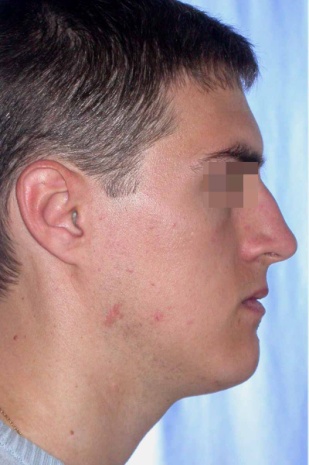

Пациент с преразвитие на долната челюст (мандибуларен прогнатизъм) – преди и след реконструкция на долната челюст - случай на доц. Джоров.